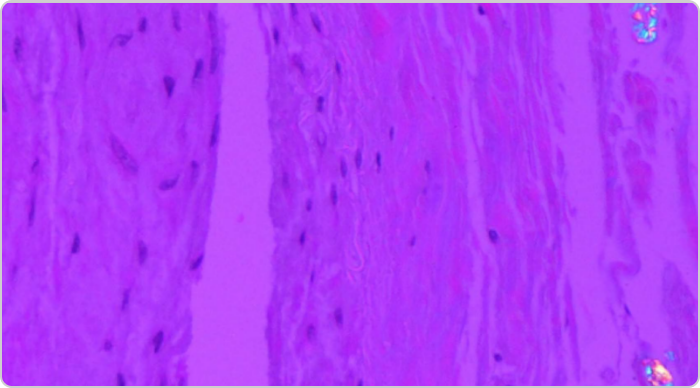

High power view of a tophus

High-power view of a tophus, with central urate deposition surrounded by mononuclear inflammatory cells and scattered giant cells.1

Adapted from Nickeleit V, et al. Nephrol Dial Transplant. 1997;12:1832-1838.

KRYSTEXXA has not been studied to reverse damage to the kidneys or any of the body's organs.

Side by side gouty tophi images

Gouty tophus in renal medulla (left; acid fuchsin – orange G stain, x125 original magnification). Center of a tophus with uric acid crystals (right; polarized light; x140 original magnification).1